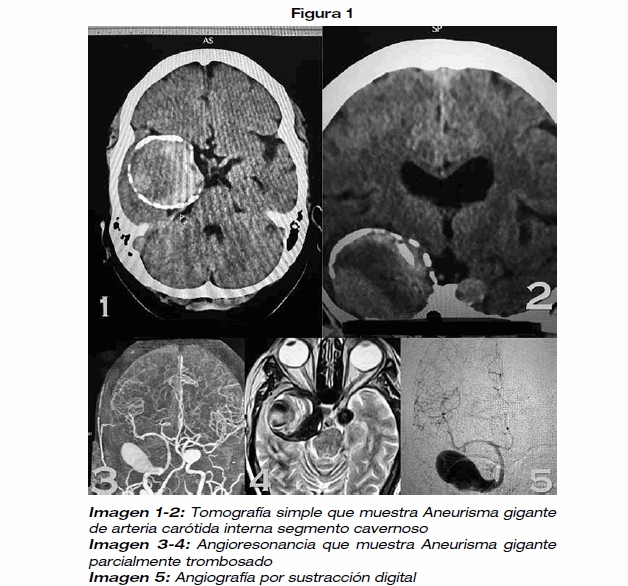

<body><![CDATA[<p align="justify"><font face="Verdana, Arial, Helvetica, sans-serif" size="2">Vía aérea: apertura oral 3 cm, diámetro esternomentoniano 11cm, diámetro tiromentoniano 5 cm, Mallampati II, línea de cruce anterior.</font></p>     <p align="justify"><font face="Verdana, Arial, Helvetica, sans-serif" size="2">Laboratorios           3/05/2018</font> <font face="Verdana, Arial, Helvetica, sans-serif" size="2">hipertrigliceridemia, resto dentro de parámetros.</font></p>     <p align="justify"><font face="Verdana, Arial, Helvetica, sans-serif" size="2">Valoración cardiológica 3/05/2018 reporta enfermedad de Chagas por epidemiología, con riesgo Goldman II/IV. En el electrocardiograma se evidencia bloqueo AV de II grado Mobitz tipo 1.</font></p>     <p align="justify"><font face="Verdana, Arial, Helvetica, sans-serif" size="2">Se clasifica a la paciente como ASA 3, aneurisma cerebral gigante, sobrepeso, hipertensión arterial en tratamiento, hipotiroidismo en tratamiento, insuficiencia venosa superficial grado II, hipertrigliceridemia en tratamiento, bloqueo AV de II grado.</font></p>     <p align="justify"><font face="Verdana, Arial, Helvetica, sans-serif" size="2">En la exploración neurológica destaca parestesias y dolor en territorio de V par del lado derecho además de parálisis completa de III del mismo lado derecho, amaurosis y defecto pupilar aferente del lado derecho. Los estudios de imagen mostraban una lesión expansiva extraaxial basal frontotemporal derecha</font> <font face="Verdana, Arial, Helvetica, sans-serif" size="2">con calcificaciones periféricas de probable origen vascular, por lo cual se realizó una angiografía cerebral que confirmo una lesión aneurismática del segmento cavernoso de ambas arterias carótidas internas, siendo la del lado derecho un aneurisma gigante con dimensiones de cuello domo de 52,4mm., anteroposterior 27,5mm. También se complementó con una IRM</font> <font face="Verdana, Arial, Helvetica, sans-serif" size="2">de encéfalo con contraste que mostraba la imagen típica de un aneurisma gigante parcialmente trombosado con imágenes en capas de cebolla. Se realizo junta con equipo de cirugía endovascular llegando a la conclusión que la mejor opción por el tipo de lesión era la microcirugía a través de una ByPass Extra - Intracraneal de alto flujo con injerto de arteria radial.</font></p>     <p align="center"><img src="/img/revistas/rmcmlp/v26n2/a08_figura_01.gif" width="628" height="586"></p>     <p align="justify"><font face="Verdana, Arial, Helvetica, sans-serif" size="2">Se realizó anestesia total intravenosa. La inducción con: Remifentanil 0.3 ug/kg/ min (24 ml/h), Propofol 100 mg, rocuronio 50 mg iv, se espera tiempo de latencia, ventilación manual a  presión  positiva y se  procede  a</font> <font face="Verdana, Arial, Helvetica, sans-serif" size="2">laringoscopia, Cormack Lehane I, intubación orotraqueal con tubo No 7.5, Se verifica ventilación simétrica en ambos hemitórax y se fija a #21 cm; se conecta a VM AC, VT: 400 ml, FR 12 cpm, R: I/E 1:2, PEEP 5 cmH2O</font></p>     <p align="center"><img src="/img/revistas/rmcmlp/v26n2/a08_figura_02.gif" width="622" height="536"></p>     <p align="justify"><font face="Verdana, Arial, Helvetica, sans-serif" size="2">Se realiza protección ocular, ótica, de puntos de apoyo y de presión. Se instala línea arterial en arteria radial derecha con bránula No 20. Se instala otra vía periférica miembro superior derecho B# 16, catéter venoso central subclavio izquierdo, primer intento, sin complicaciones. Se realiza bloqueo Scalp derecho con bupivacaina mas epinefrina 0.25% 30 mg, 30 ug, mas lidocaína 120 mg.</font></p>     <p align="justify"><font face="Verdana, Arial, Helvetica, sans-serif" size="2">Mantenimiento. Propofol 50-69 ug/kg min, total 2771 mg, remifentanil 0.1-0.19 ug / kg/min, total 7915ug, total rocuronio 80 mg</font></p>     ]]></body>